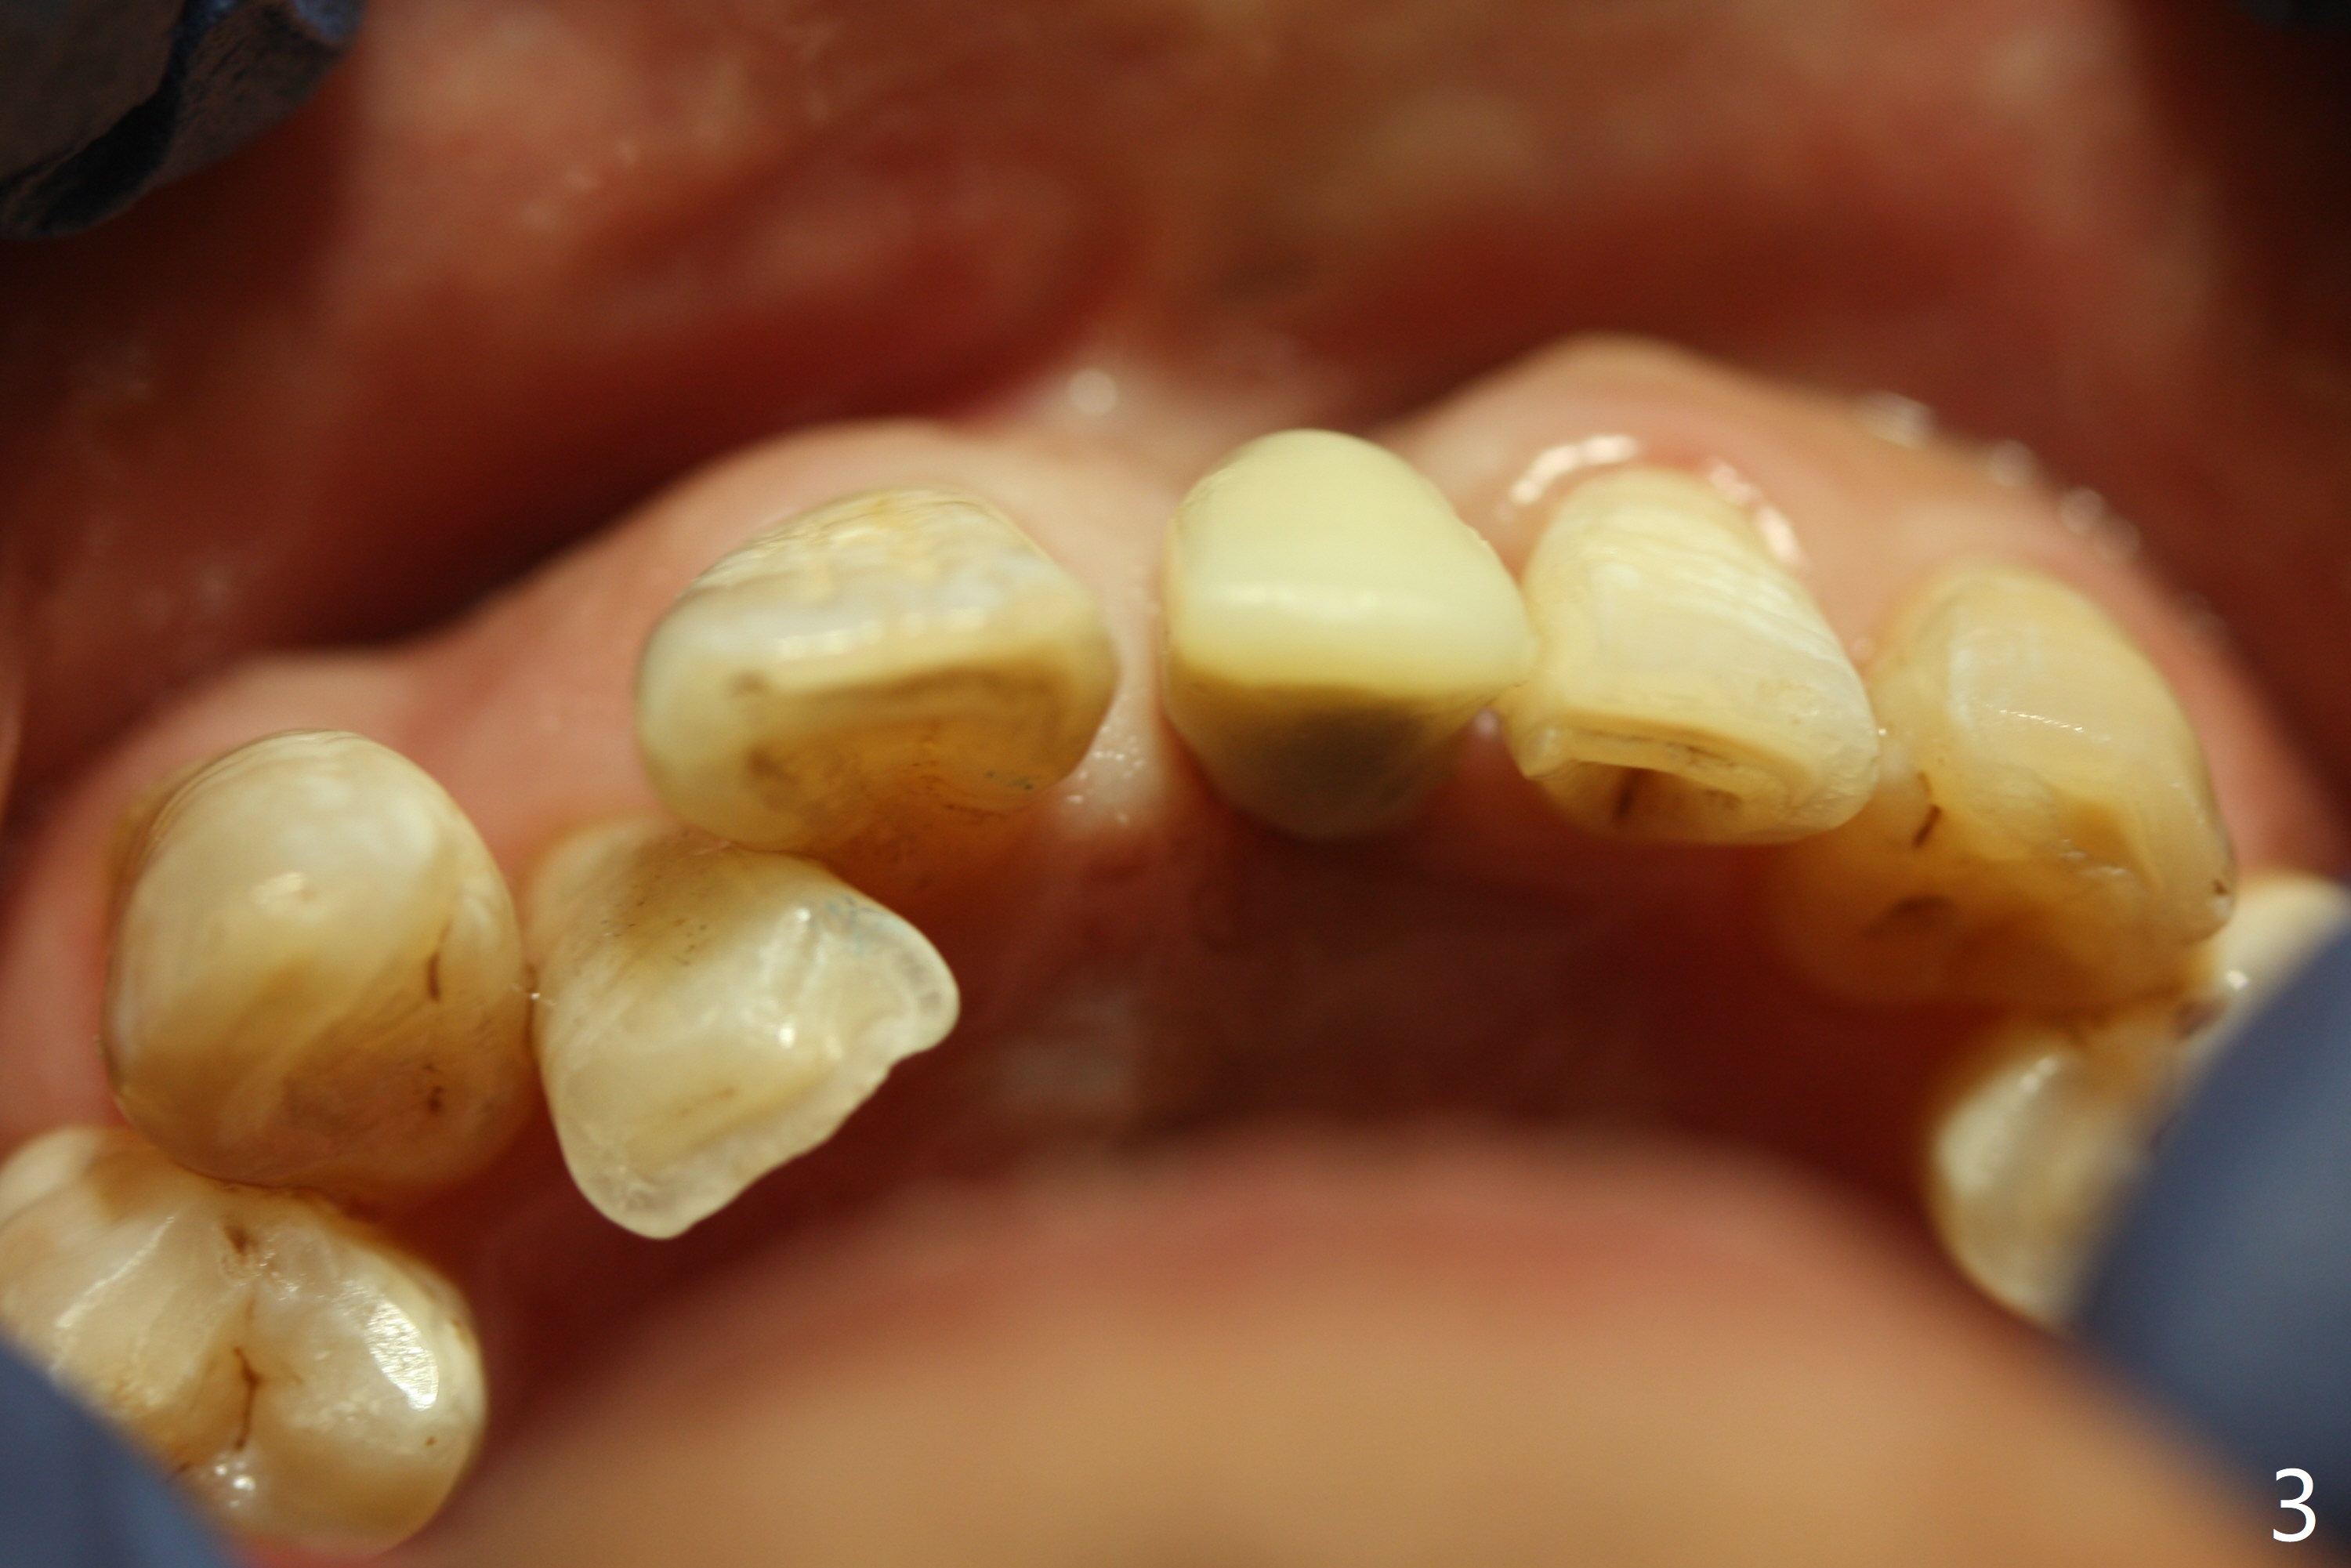

Reduction